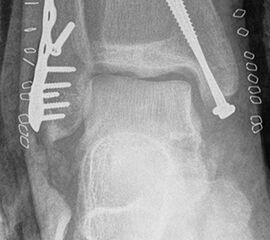

Seit einer Untersuchung von Nelson und Jensen aus dem Jahre 1940 wird allgemein akzeptiert, dass die Indikation zur Osteosynthese des Tibiahinterkantenfragments nur dann besteht, wenn die Größe mehr als ein Drittel (nach zahlreichen Autoren auch ein Viertel) der Gelenkfläche beträgt (Abbildung 15) 25. Dieses bis heute allgemeinakzeptierte Vorgehen basiert auf der Beobachtung von lediglich acht unterschiedlich versorgten Patienten. Seither gibt es keine weiteren klinischen Studien, die dieses Vorgehen stützen. Mittlerweile gibt es allerdings zunehmend Hinweise, dass bei der Versorgung des posterioren Malleolus viele andere Faktoren eine wichtige Rolle spielen 26. Da an der Tibiahinterkante das Lig. tibiofibulare posterius ansetzt (Abbildung 16), wird durch die offene Reposition und Stabilisierung die Integrität und die physiologische Spannung der hinteren Syndesmose rekonstruiert (Abbildung 17). Dies ist entscheidend für die anatomische Reposition der Fibula in der Tibiainzisur.

Gardner et al. konnten beispielsweise zeigen, dass die offene anatomische Reposition der Tibiahinterkante der Stabilisierung mittels Stellschraube überlegen war und gleichzeitig mit einer geringeren Rate an postoperativen Fehlstellungen der Fibula in der CT-Kontrolle einherging 2728. Aus Sicht der Autoren ist prinzipiell die Stabilisierung über eine direkte Reposition indiziert, wenn die Größe des Fragmentes dies erlaubt. Bei gleichzeitigem Vorliegen einer Fraktur des lateralen und/oder medialen Malleolus sollte zunächst die Versorgung der des Tibiahinterkantenfragments erfolgen. Dies erlaubt die radiologische Kontrolle der Reposition und Osteosynthese-Lage, welche durch eine zuvor aufgebrachte Fibula-Platte häufig erschwert ist 29. Dafür werden die Patienten in Seitenlage gelagert. Dies erlaubt die direkte Versorgung der posterioren Malleolusfraktur über einen posterolateralen Zugang 30. Das sehr kräftige Periost wird im Frakturverlauf inzidiert und aus den Frakturspalt entfernt, so kann eine anatomische Reposition erfolgen. Entsprechend der Fragmentgröße erfolgt entweder die Versorgung mittels Drittelrohrplatte in Antiglide-Technik oder eine Zugschraubenosteosynthese. Die Versorgung der Fibula-Fraktur gelingt über den gleichen Zugang. Zur Versorgung des medialen Malleolus wird der Patient auf den Rücken umgelagert. Dies kann bei entsprechender Vorbereitung ohne erneutes steriles Abdecken erfolgen. Durch dieses Vorgehen konnte im eigenen Kollektiv die Notwendigkeit einer Stabilisierung der Syndesmose mit Stellschraube/Tight Rope deutlich reduziert werden.